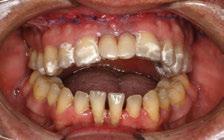

Presentamos el caso de un paciente de 66 años de edad, ASA I, que acudió a nuestra consulta para rehabilitar la arcada superior, buscando una solución definitiva para recuperar tanto la función como la estética perdida. El paciente presentaba buen estado de salud general, no refería alergias medicamentosas ni medicación relevante.

-Registros fotográficos intra y extraorales (Figura 1 a-c).

A partir del estudio radiológico y de las imágenes fotográficas podemos observar edentulismo de 17, 15, 14, 12,

Figura 1a. Foto intraoral frontal inicial.

Figura 1b. Foto intraoral lateral izquierda inicial.

Figura 1c. Foto intraoral lateral derecha inicial.

25, 26, 28, 37, 38, 47 y 48. Presentaba corona desajustada en 13 con extensión en 12, implantes en 35-36, 45-46, con coronas ferulizadas en 35-36, 45-46, y dientes anteriores superiores con enfermedad periodontal Grado IV.

2. Exploración de tejidos blandos

El paciente presentaba biotipo periodontal grueso, con márgenes asimétricos, con recesiones gingivales a nivel de 11 y 13 y pérdida de tejidos blandos interproximales.

3. Exploración de tejidos duros

En la exploración radiográfica (OPG, CBCT) observamos la existencia de pérdida ósea interproximal, lesión apical a nivel de la raíz mesial del 27 y el cordal del primer cuadrante incluido y neumatización sinusal del primer y segundo cuadrante.

En el CBCT observamos pérdida ósea posterior superior debida a la neumatización de los senos maxilares izquierdo y derecho. También podemos observar disponibilidad ósea apical suficiente en dientes antero-superiores para la realización de una Implantología inmediata y corticales vestibulares y palatinas conservadas.